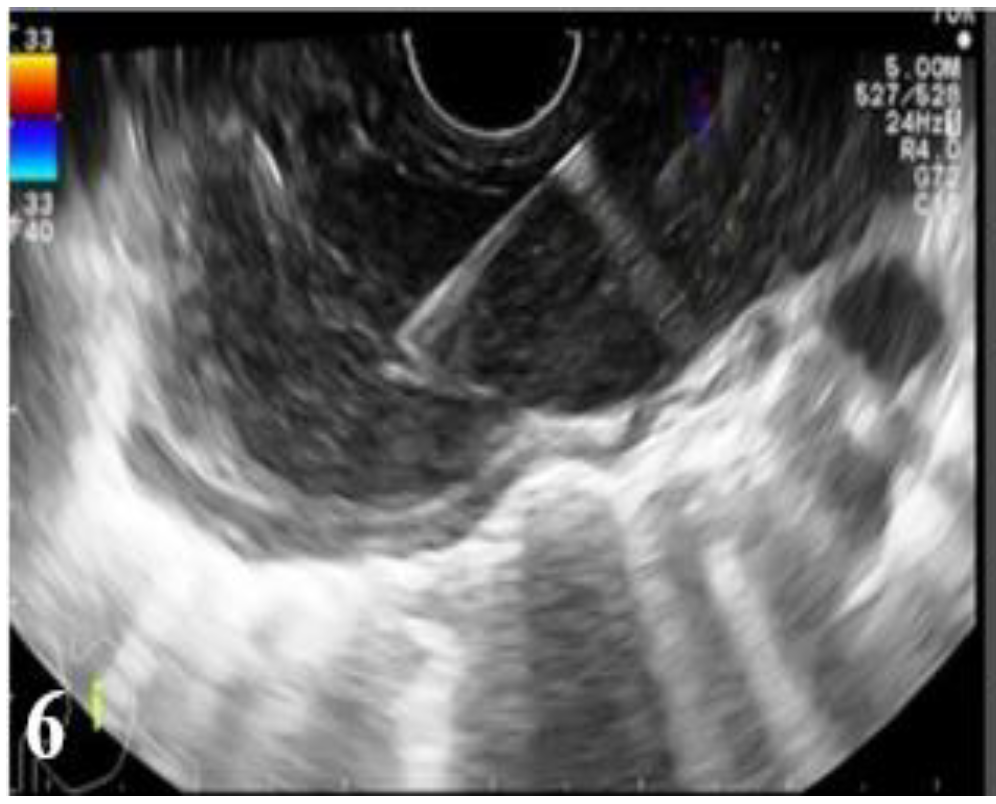

Figure 6.

EUS images: endoscopically guided fine needle aspiration (FNA) biopsy of a malignant mediastinal adenopathy from an esophageal carcinoma (part 2).